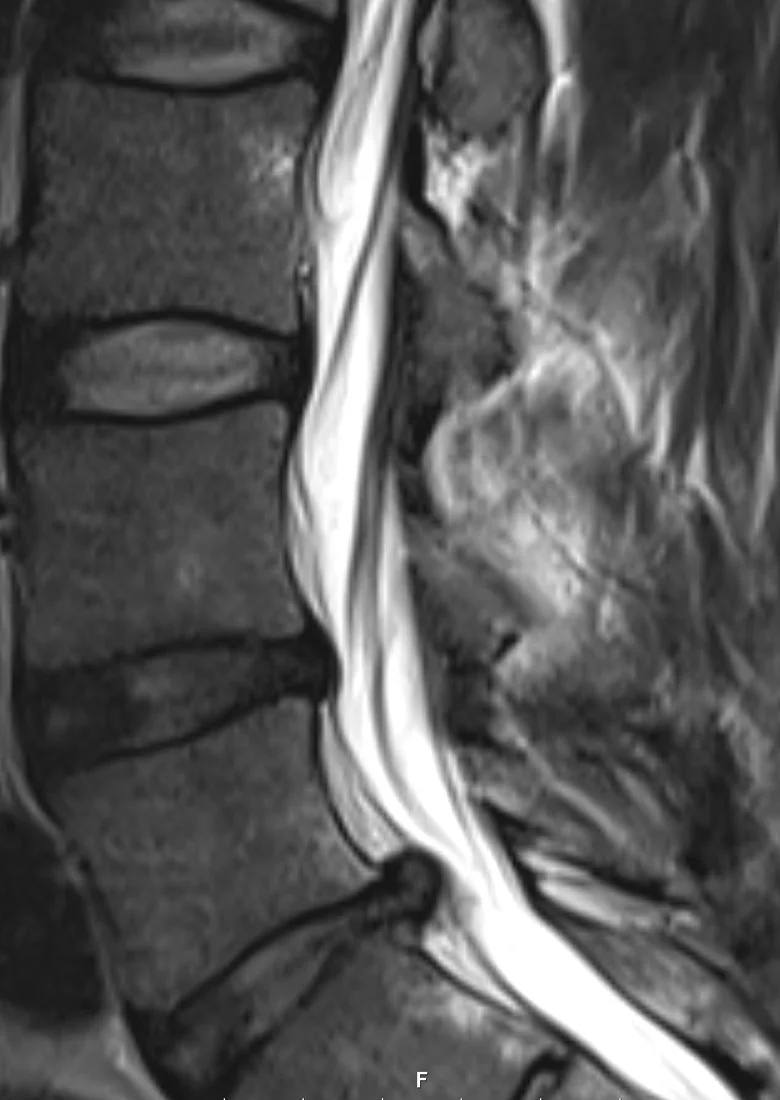

Vaivaksi jäi puutunut ja heikko jalka. Reisi hieman puutunut, pohje ja jalan ulkosyrjä sekä ulommat varpaat puutuneimmat. Kävin itse MRIssä kun ei lähetettä saanut. Pullistuma painaa (L5) S1 juuren tyvialuetta.